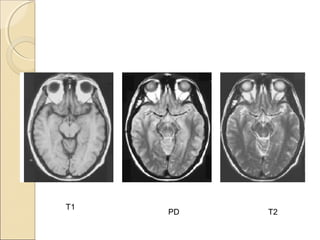

Proton density imagingProton density imaging

A proton density image is one where the

difference in the numbers of protons per

unit volume in the patient is the main

determining factor in forming image

contrast.

Proton density weighting is always

present to some extent.

Long TR and short TE

In order to achieve proton density

weighting, the effects of T1 and T2

contrast must be diminished,

so that proton density weighting can

dominate.

A long TR allows tissues e.g. fat and

water to fully recover their longitudinal

magnetisation and therefore diminishes

T1 weighting.

A short TE does not give fat or water

time to decay and therefore diminishes

T2 weighting

T1

PD T2